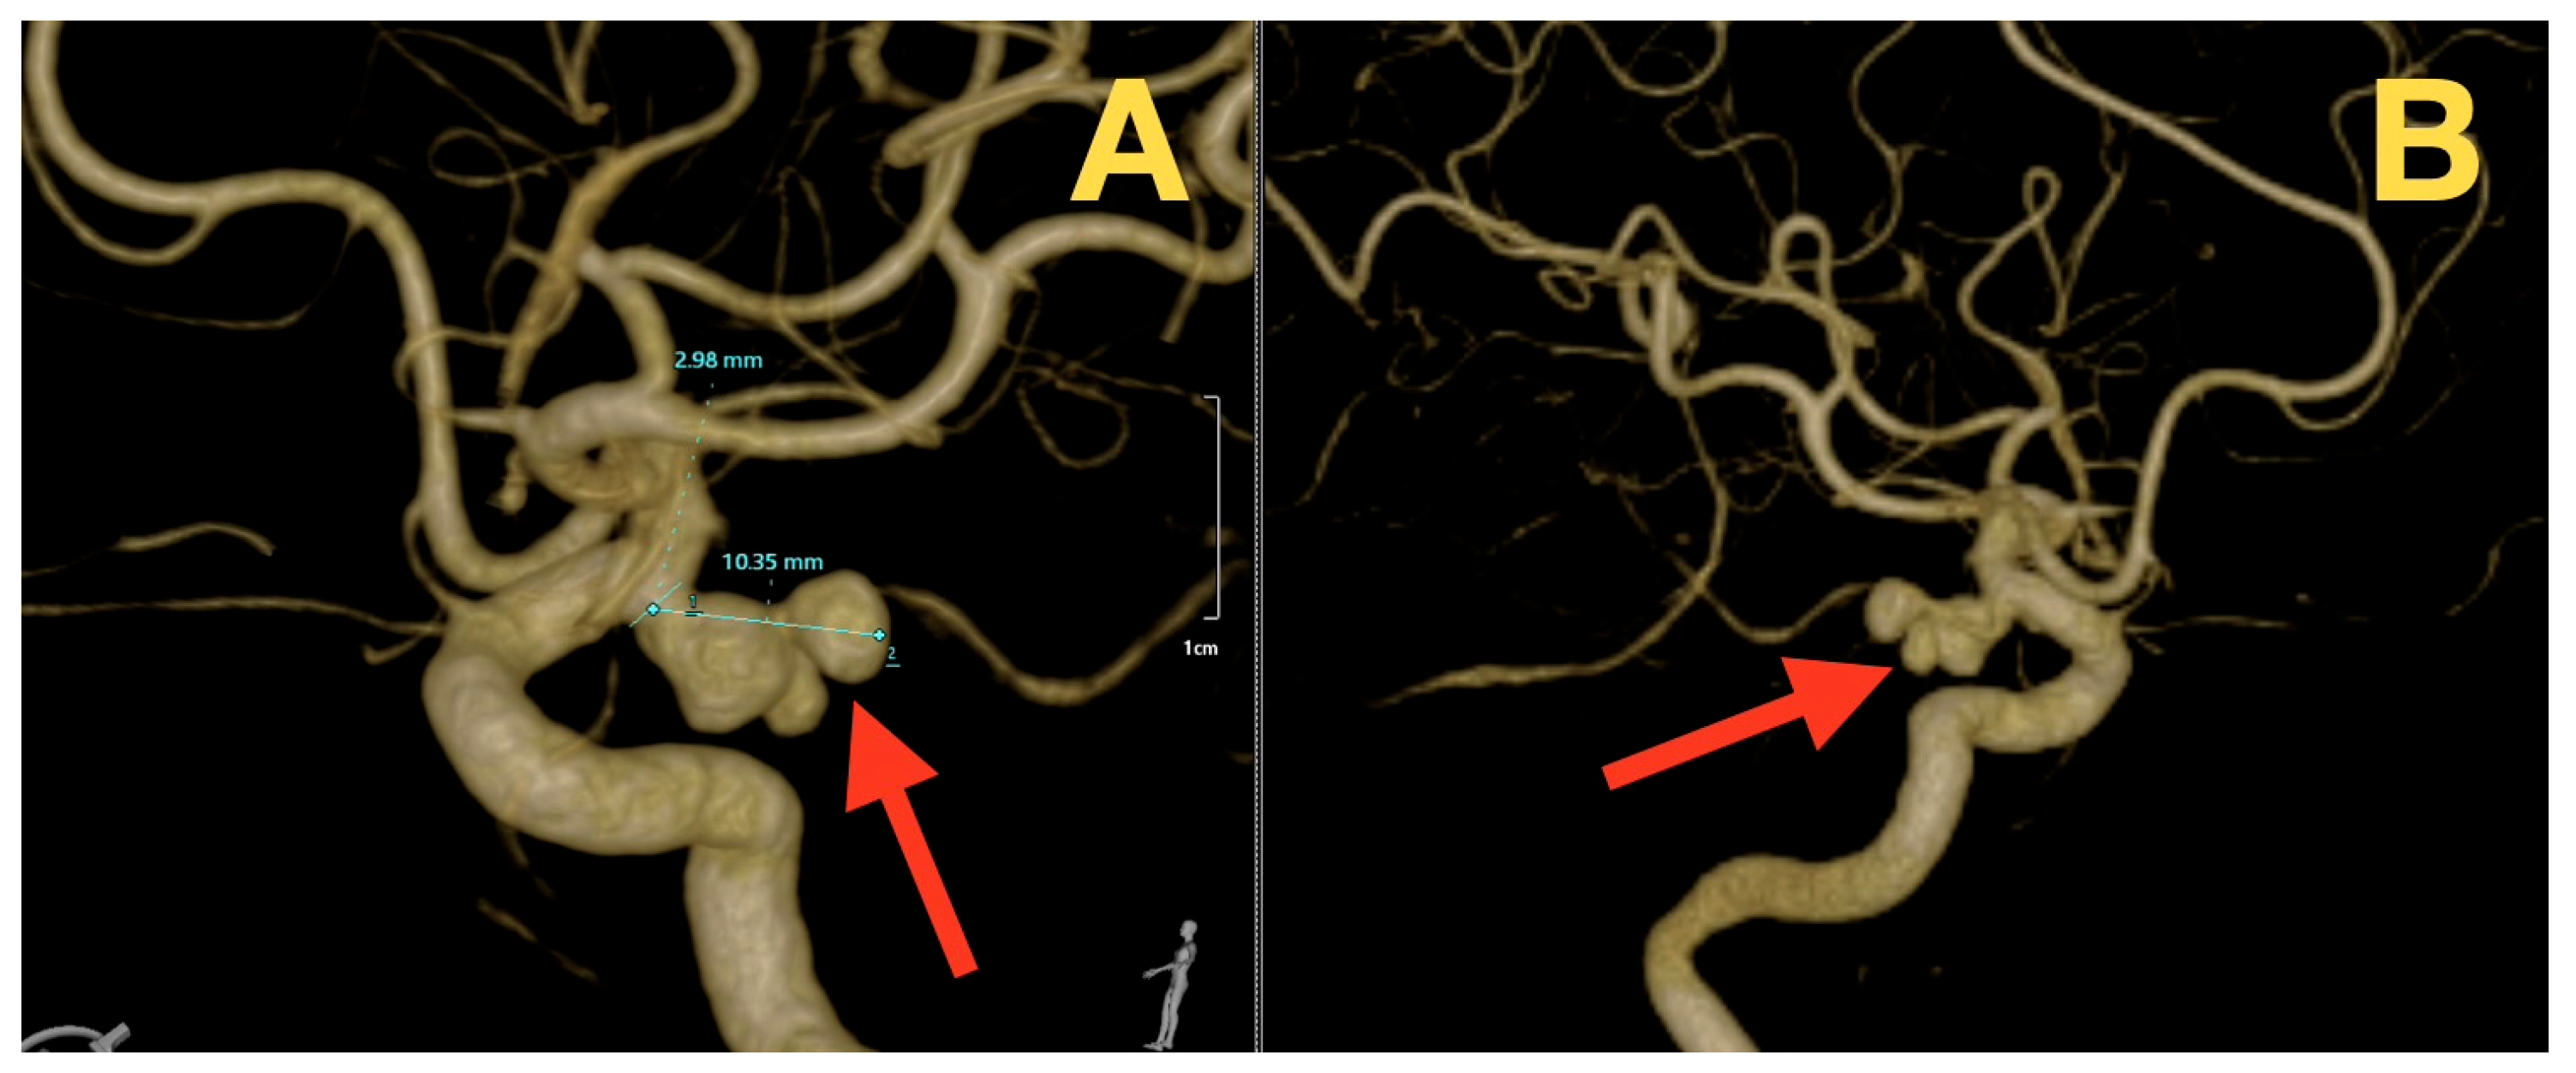

2. Case Presentation